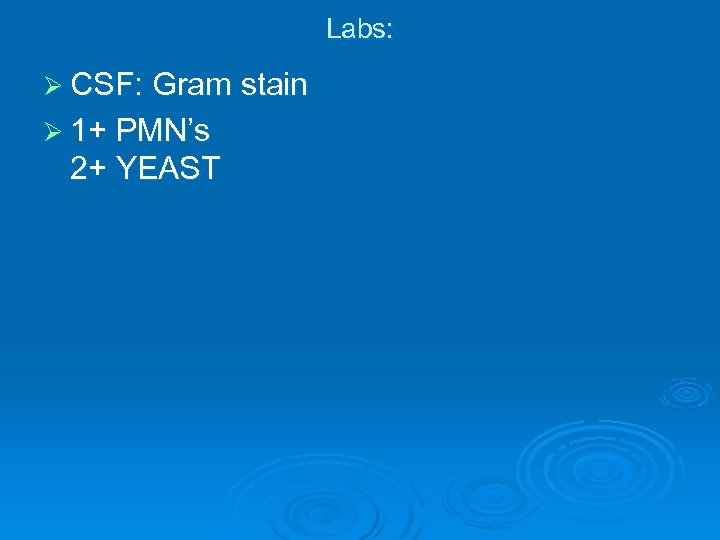

Labs: Ø CSF: Gram stain Ø 1+ PMN’s 2+ YEAST